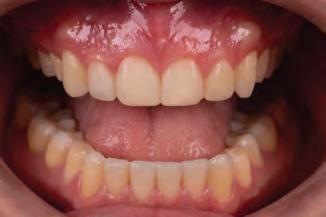

A 31-year-old woman presented with cosmetic concerns regarding her smile and requested a conservative enhancement. After clinical and radiographic analysis, digital 35mm photographs were taken and reviewed by the restorative clinician, technician, and surgeon (Fig 1). A digital impression was taken of the maxillary and mandibular arches using an intraoral scanner (Trios 3, 3Shape; Fig 2), and a smile design was developed with NemoSmile Design 3D software (Nemotec; Fig 3a). This allows for a facially driven smile frame to be created using reference lines of facial and smile proportions and natural teeth shapes and textures from the digital library (Fig 3b).

After developing the simulated mock-up, a 3D-printed resin model was created using CAD software (Fig 4a), and a clear PVS matrix (Exaclear, GC America) was fabricated to replicate the printed diagnostic wax-up using a nonperforated tray (Fig

Fig 1 Preoperative clinical views of a 31-year-old woman presenting with diastemas and limited tooth visibility. (top) Portrait. (center row) Intraoral views. (bottom row) Smile.

4b). This matrix was used to create an intraoral motivational mock-up with bis-acryl composite (Luxatemp Ultra, DMG). This additive mock-up provides the interdisciplinary team with an intraoral translation for evaluation (Fig 5). Upon evaluation of the digital smile frame and the clinical translation, it was determined that multiple esthetic and restorative requirements were necessary for an optimal biologic framework, and the interdisciplinary team determined the best sequence for these procedures. The patient was presented with the interdisciplinary treatment possibilities that included restoring the maxillary anterior teeth and premolars with a minimally

invasive preparationless procedure or with less conservative veneer preparations. The restorative materials discussed included injectable resin composites and ceramic (ie, feldspathic, pressable, machinable). For an optimal biologic framework and health, it was determined that connective tissue grafting would be necessary for treatment of the recessiontype defects on the maxillary left central and lateral incisors, canine, and premolars. The patient opted for the conservative preparationless composite veneers using the injectable resin technique followed by a connective tissue surgical procedure using the tunneling technique.